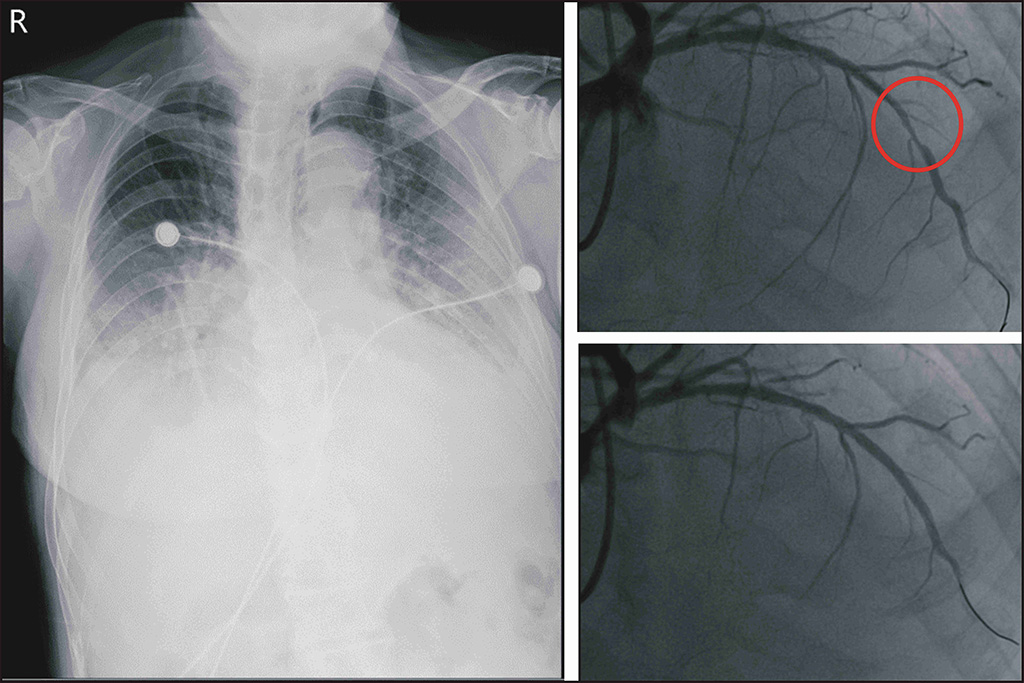

病人到院時,只要一點動作就呼吸費力,且持續有胸悶感覺。心電圖的結果竟然是急性心肌梗塞,彰基急診團隊立即連絡心臟內科團隊,緊急啟動心導管檢查。然而病人卻無法躺平,坐立難安,X光顯示有嚴重的肺水腫,突然變成呼吸衰竭的狀況,於是施行氣管插管,維持病人的呼吸,隨後心導管顯示嚴重冠狀動脈阻塞。所幸經由置放支架後,目前病人已拔管且血氧濃度百分之百,穩定治療中。

患者X光顯示肺水腫(左圖)、冠狀動脈嚴重狹窄(右上圖)、打通後血流恢復(右下圖)。